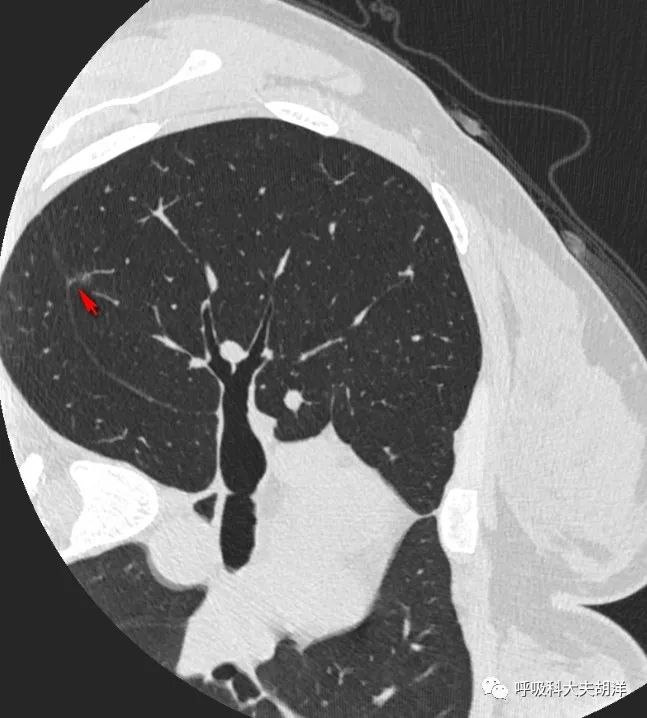

但这个结节偏恶性的特征还不止于此,上图结节的左面有一条线,这个是斜裂,斜裂是胸膜的一种延续,这个胸膜在靠近结节的部分微微向结节隆起,似乎有牵拉,这一层面看不明显,下图就比较明显了,箭头所指的部位是结节底部牵拉胸膜的征象,这是结节恶性特征的另外一个征象。

向下滑动查看上面三张图片则非常直观的看到结节牵拉斜裂的表现,结节靠近斜裂的地方像是被斜裂吸引,斜裂靠近结节的地方像是被结节吸引,整体上就像快要落山的太阳,太阳和水里的太阳的倒影几乎快连成一片,这是比较典型的胸膜牵拉。

如果想看结节和血管之间的关系,下面这几张图更加明显一点,下面前两张红箭头指的是结节,周围枝枝叉叉的都是血管,有些血管和结节长到了一起,尤其是最后一张图,另一个红箭头指着的血管长进了血管,这是结节代谢高,需要更多血液供应的表现,也是恶性肿瘤的一个表现。